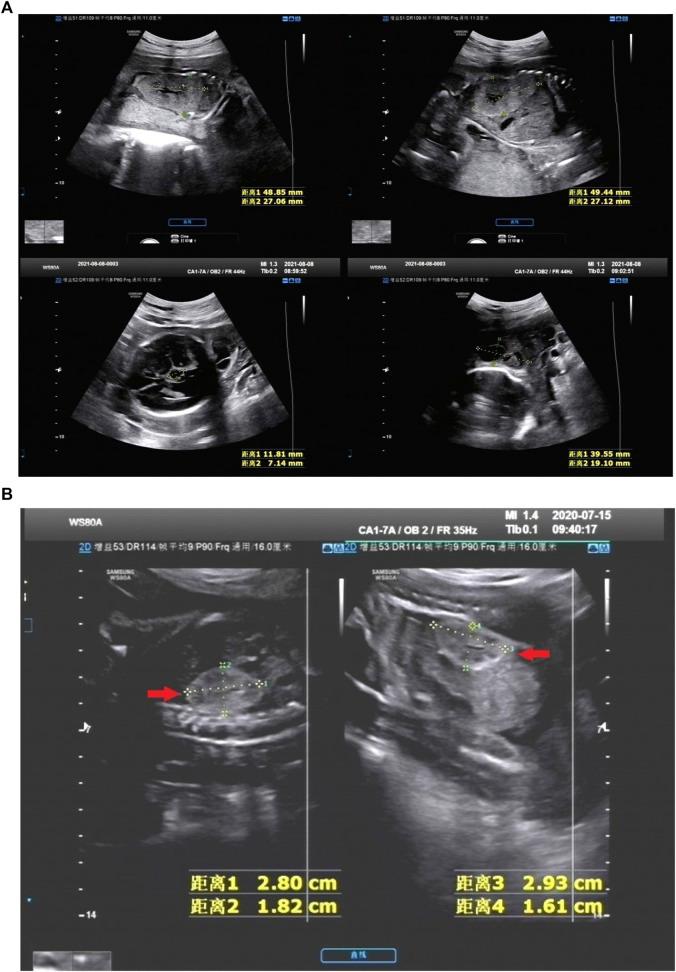

To investigate the positive rate of chromosomal and monogenic etiologies and pregnancy outcomes in fetuses with hyperechoic kidney, and to provide more information for genetic counseling and prognosis evaluation. We performed a retrospective analysis of 25 cases of hyperechoic kidney diagnosed prenatal in the Second Affiliated Hospital of Harbin Medical University and Harbin Red Cross Central Hospital (January 2017-December 2022). Furthermore, we conducted a meta-analysis of a series of hyperechoic kidneys (HEK) in the literature to assess the incidence of chromosomal and monogenic etiologies, mortality, and pooled odds ratio (OR) estimates of the association between the incidence of these outcomes and other associated ultrasound abnormalities. 25 fetuses of HEK were enrolled in the cohort study, including 14 with isolated hyperechoic kidney (IHK) and 11 with non-isolated hyperechoic kidney (NIHK). Chromosomal aneuploidies were detected in 4 of 20 patients (20%). The detection rate of pathogenic or suspected pathogenic copy number variations (CNVs) was 29% (4/14) for IHK and 37% (4/11) for NIHK. Whole exome sequencing (WES) was performed in 5 fetuses, and pathogenic genes were detected in all of them. The rate of termination of pregnancy was 56% in HEK. 21 studies including 1,178 fetuses were included in the meta-analysis. No case of abnormal chromosome karyotype or (intrauterine death)IUD was reported in fetuses with IHK. In contrast, the positive rate of karyotype in NIHK was 22% and that in HEK was 20%, with the ORs of 0.28 (95% CI 0.16-0.51) and 0.25, (95% CI 0.14-0.44), respectively. The positive rate of (chromosome microarray analysis) CMA in IHK was 59% and that in NIHK was 32%, with the ORs of 1.46 (95% CI 1.33-1.62) and 0.48 (95% CI, 0.28-0.85), respectively. The positive rate of monogenic etiologies in IHK was 31%, with the OR of 0.80 (95% CI 0.25-2.63). In IHK, the termination rate was 21% and neonatal mortality was 13%, with the ORs of 0.26 (95% CI, 0.17-0.40), 1.72 (95% CI, 1.59-1.86), and that in NIHK was 63%, 0.15 (95% CI, 0.10-0.24); 11%, 0.12 (95% CI, 0.06-0.26), respectively. The intrauterine mortality in NIHK group was 2%, with the OR of 0.02 (95% CI, 0.01-0.05). variant has the highest incidence (26%) in IHK. The positive rate of karyotype was 20% in HEK and 22% in NIHK. The positive rate of CMA was 32% in NIHK and 59% in IHK. The positive rate of IHK monogenic etiologies was 31%. gene variation is the most common cause of IHK. The overall fetal mortality rate of NIHK is significantly higher than that of IHK. The amount of amniotic fluid, kidney size and the degree of corticomedullary differentiation have a great impact on the prognosis, these indicators should be taken into consideration to guide clinical consultation and decision-making.

为研究高回声肾胎儿的染色体和单基因病因阳性率及妊娠结局,为遗传咨询和预后评估提供更多信息。我们对哈尔滨医科大学附属第二医院和哈尔滨红十字中心医院2017年1月至2022年12月期间产前诊断为高回声肾的25例病例进行了回顾性分析。此外,我们对文献中一系列高回声肾(HEK)进行了荟萃分析,以评估染色体和单基因病因的发生率、死亡率以及这些结局发生率与其他相关超声异常之间关联的合并比值比(OR)估计值。25例高回声肾胎儿纳入队列研究,其中14例为孤立性高回声肾(IHK),11例为非孤立性高回声肾(NIHK)。20例患者中有4例(20%)检测到染色体非整倍体。IHK的致病性或疑似致病性拷贝数变异(CNV)检出率为29%(4/14),NIHK为37%(4/11)。对5例胎儿进行了全外显子组测序(WES),均检测到致病基因。高回声肾胎儿的妊娠终止率为56%。荟萃分析纳入了21项研究,共1178例胎儿。IHK胎儿未报告染色体核型异常或宫内死亡(IUD)病例。相比之下,NIHK的核型阳性率为22%,HEK为20%,OR分别为0.28(95%CI 0.16 - 0.51)和0.25(95%CI 0.14 - 0.44)。IHK的染色体微阵列分析(CMA)阳性率为59%,NIHK为32%,OR分别为1.46(95%CI 1.33 - 1.62)和0.48(95%CI 0.28 - 0.85)。IHK单基因病因的阳性率为31%,OR为0.80(95%CI 0.25 - 2.63)。在IHK中,终止妊娠率为21%,新生儿死亡率为13%,OR分别为0.26(95%CI 0.17 - 0.40)、1.72(95%CI 1.59 - 1.86),NIHK的分别为63%、0.15(95%CI 0.10 - 0.24);11%、0.12(95%CI 0.06 - 0.26)。NIHK组的宫内死亡率为2%,OR为0.02(95%CI 0.01 - 0.05)。变异在IHK中的发生率最高(26%)。HEK的核型阳性率为20%,NIHK为22%。NIHK的CMA阳性率为32%,IHK为59%。IHK单基因病因的阳性率为31%。基因变异是IHK最常见的原因。NIHK的总体胎儿死亡率显著高于IHK。羊水量、肾脏大小和皮质髓质分化程度对预后有很大影响,这些指标应在指导临床咨询和决策时予以考虑。